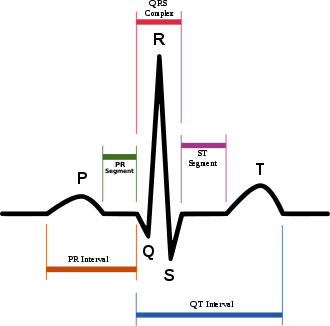

Biomedical engineering has recently emerged as its own study, as compared to many other engineering fields. Such an evolution is common as a new field transition from being an interdisciplinary specialization among already-established fields to being considered a field in itself. Much of the work in biomedical engineering consists of research and development, spanning a broad array of subfields (see below). Prominent biomedical engineering applications include the development of biocompatible prostheses, various diagnostic and therapeutic medical devices ranging from clinical equipment to micro-implants, common imaging equipment such as MRIs and EKG/ECGs, regenerative tissue growth, pharmaceutical drugs and therapeutic biologicals.

Imaging technologies are often essential to medical diagnosis, and are typically the most complex equipment found in a hospital including: fluoroscopy, magnetic resonance imaging (MRI), nuclear medicine, positron emission tomography (PET), PET-CT scans, projection radiography such as X-rays and CT scans, tomography, ultrasound, optical microscopy, and electron microscopy.